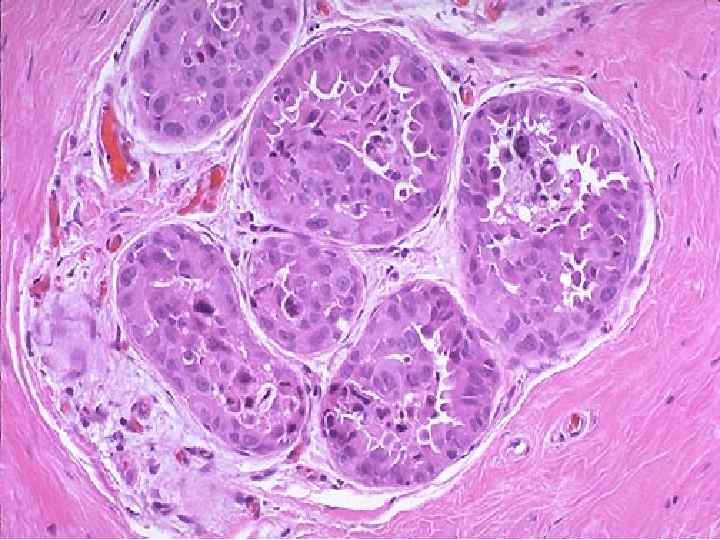

Семинома